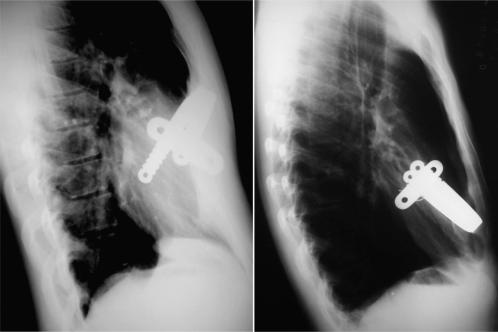

To compare bar displacement and complication rates in three retrospective series of patients operated on by the same surgical team.

A retrospective medical chart analysis of the three patient series was performed. In the first series, the original, unmodified Nuss technique was performed. In the second, we used the ''third point fixation'' technique,and in the last series, the correction was performed with modifications to the stabilizer and stabilizer position.

There were no deaths in any of the series. Minor complications occurred in six (4.9%) patients: pneumothorax with spontaneous resolution (2), suture site infection (2), and bar displacement without the reoperation need (2). Major complications were observed in eight (6.5%) patients: pleural effusion requiring drainage (1), foreign body reaction to the bar (1), pneumonia and shock septic (1), cardiac perforation (1), skin erosion/seroma (1), and displacement that necessitated a second operation to remove the bar within the 30 days of implantation (3). All major complications occurred in the first and second series.

The elimination of fixation wires, the use of shorter bars and redesigned stabilizers placed in a more medial position results in a better outcome for pectus excavatum patients treated with the Nuss technique. With bar displacement and instability no longer significant postoperative risks, the Nuss technique should be considered among the available options for the surgical correction of pectus excavatum in pediatric patients.